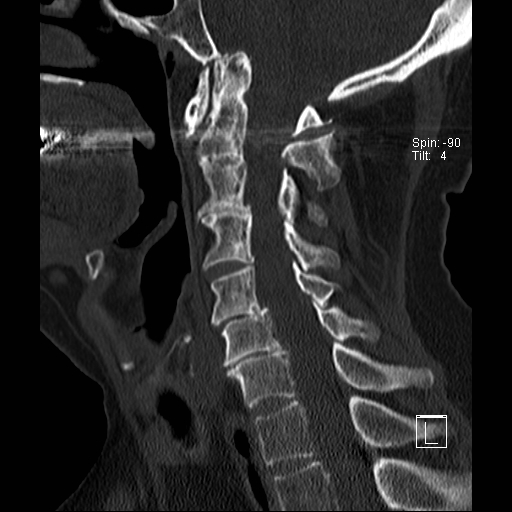

Trật khớp đội – trục

Cột sống cổ thường bị ảnh hưởng trong viêm khớp dạng thấp và có thể biểu hiện dưới dạng mất vững khớp đội – trục, trật khớp dưới trục hoặc lồng nền sọ kèm theo sụt lún sọ não.

Sụt lún sọ não xảy ra khi mỏm răng xâm lấn vào lỗ chẩm.

Trật khớp đội – trục là một biến chứng quan trọng và có thể đe dọa tính mạng của viêm khớp dạng thấp. Tình trạng này được xác định khi khoảng cách giữa mỏm răng C2 và cung đốt đội vượt quá 3 mm. Nguyên nhân là do lỏng lẻo dây chằng do viêm.

Mất vững tại khớp này có thể gây ra nhiều triệu chứng thần kinh do chèn ép tủy sống.

Hình ảnh

Khi cúi cổ, khoảng cách giữa mỏm răng và mặt sau cung trước đốt đội bị giãn rộng (14 mm) (bình thường ≤3 mm).